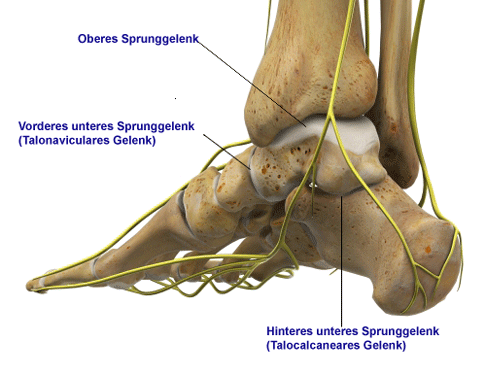

Das obere Sprunggelenk ist aus drei Gelenkpartnern zusammengesetzt. Zwei Knochen – Fibula (Wadenbein) und Tibia (Schienbein) – bilden den unterschenkelseitigen Partner. Der Talus (Sprungbein) bildet den fußseitigen Gelenkpartner. Die Sprunggelenksgabel (Malleolengabel) umgibt das kegelförmige Sprungbein (Talus). Das hintere untere Sprunggelenk (talocalcaneares Gelenk) liegt zwischen Sprungbein (Talus) und Ferse (Calcaneus). Von den beiden vorderen unteren Sprunggelenken ist hier nur das talonaviculare Gelenk (gebildet von Sprungbein und Kahnbein) zu sehen. Nicht sichtbar ist das calcaneocuboidale Gelenk zwischen Fersenbein und Würfelbein. © Viewmedica